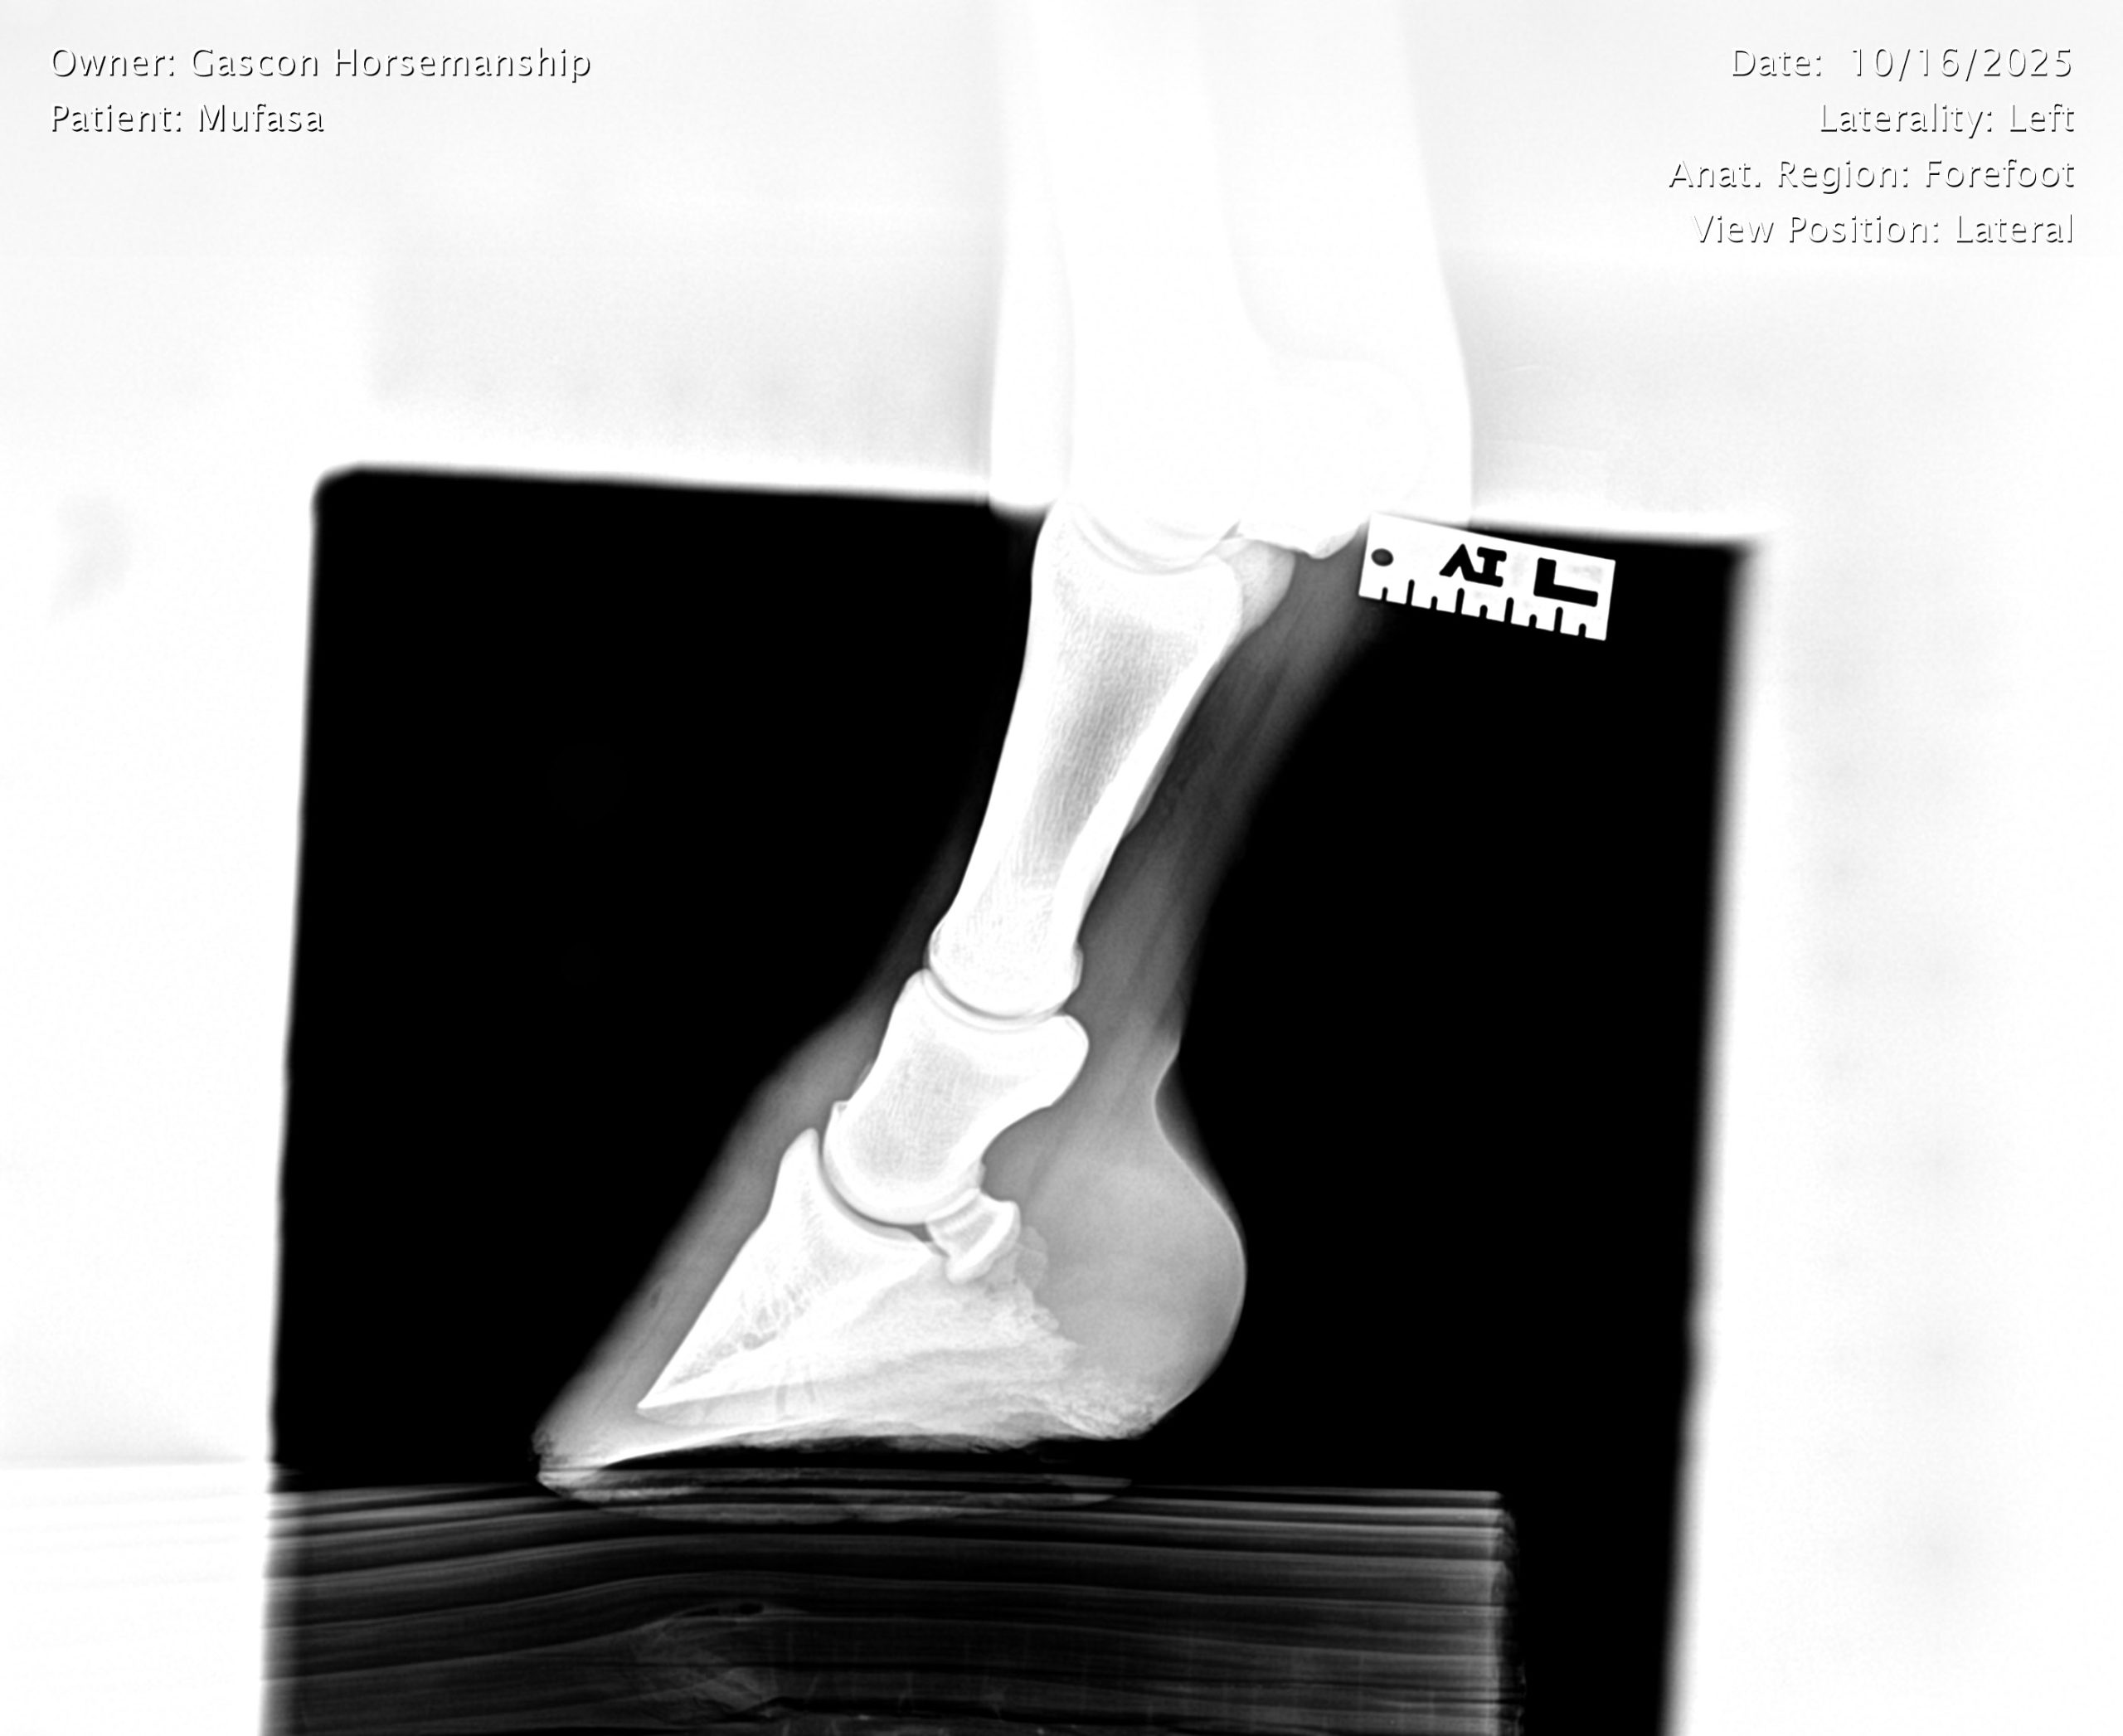

He already has a full pre-purchase exam on file, complete with 25 X-rays included in his album.